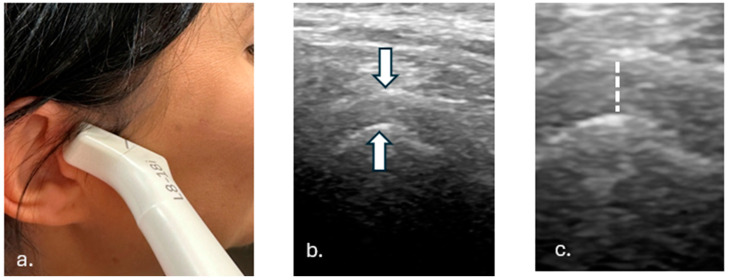

Methods: A total of 142 TMJ ultrasonographic images were segmented into three anatomical components: the mandibular condyle, joint space, and glenoid fossa. State-of-the-art architectures were tested, and the best-performing 2D Residual U-Net was trained and validated against expert annotations. The algorithm for joint space width measurement based on TMJ segmentation was proposed, calculating the vertical distance between the superior-most point of the mandibular condyle and its corresponding point on the glenoid fossa.